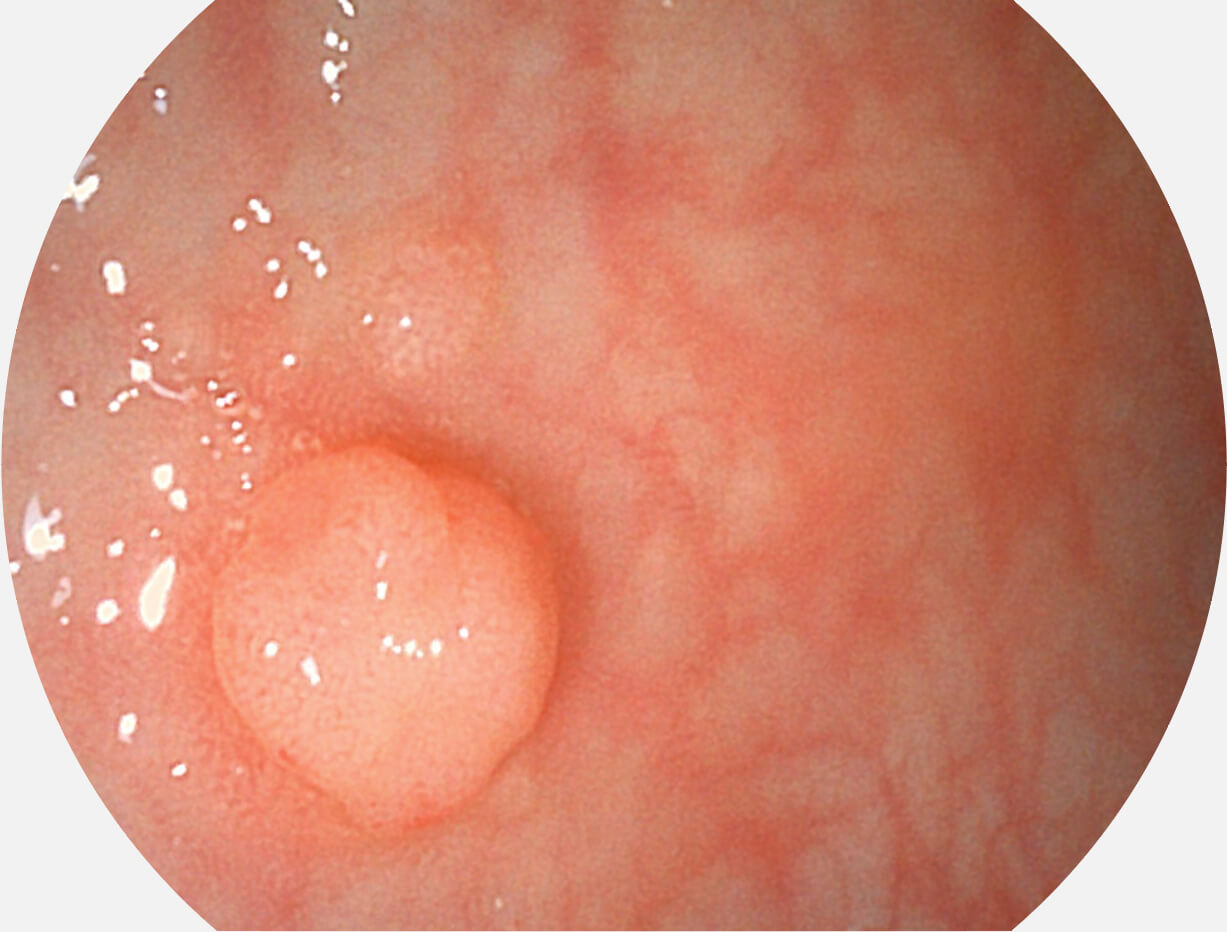

Versatile Intelligent Staining Technology, VIST

强调浅层黏膜结构的同时,保证照明亮度和提升浅层微血管与中层血管颜色对比度,病变边界更清晰。

白光图像

VIST图像